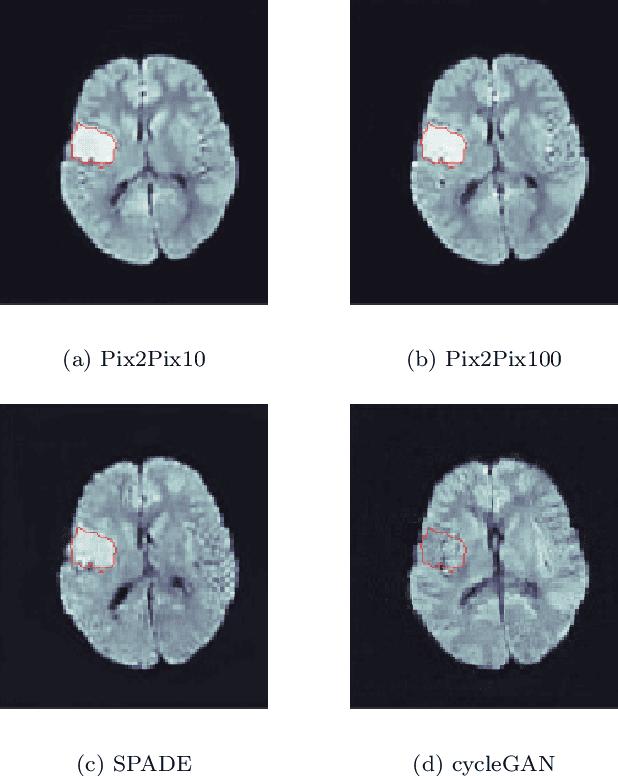

Abstract:Deep learning-based automated disease detection and segmentation algorithms promise to accelerate and improve many clinical processes. However, such algorithms require vast amounts of annotated training data, which are typically not available in a medical context, e.g., due to data privacy concerns, legal obstructions, and non-uniform data formats. Synthetic databases of annotated pathologies could provide the required amounts of training data. Here, we demonstrate with the example of ischemic stroke that a significant improvement in lesion segmentation is feasible using deep learning-based data augmentation. To this end, we train different image-to-image translation models to synthesize diffusion-weighted magnetic resonance images (DWIs) of brain volumes with and without stroke lesions from semantic segmentation maps. In addition, we train a generative adversarial network to generate synthetic lesion masks. Subsequently, we combine these two components to build a large database of synthetic stroke DWIs. The performance of the various generative models is evaluated using a U-Net which is trained to segment stroke lesions on a clinical test set. We compare the results to human expert inter-reader scores. For the model with the best performance, we report a maximum Dice score of 82.6\%, which significantly outperforms the model trained on the clinical images alone (74.8\%), and also the inter-reader Dice score of two human readers of 76.9\%. Moreover, we show that for a very limited database of only 10 or 50 clinical cases, synthetic data can be used to pre-train the segmentation algorithms, which ultimately yields an improvement by a factor of as high as 8 compared to a setting where no synthetic data is used.